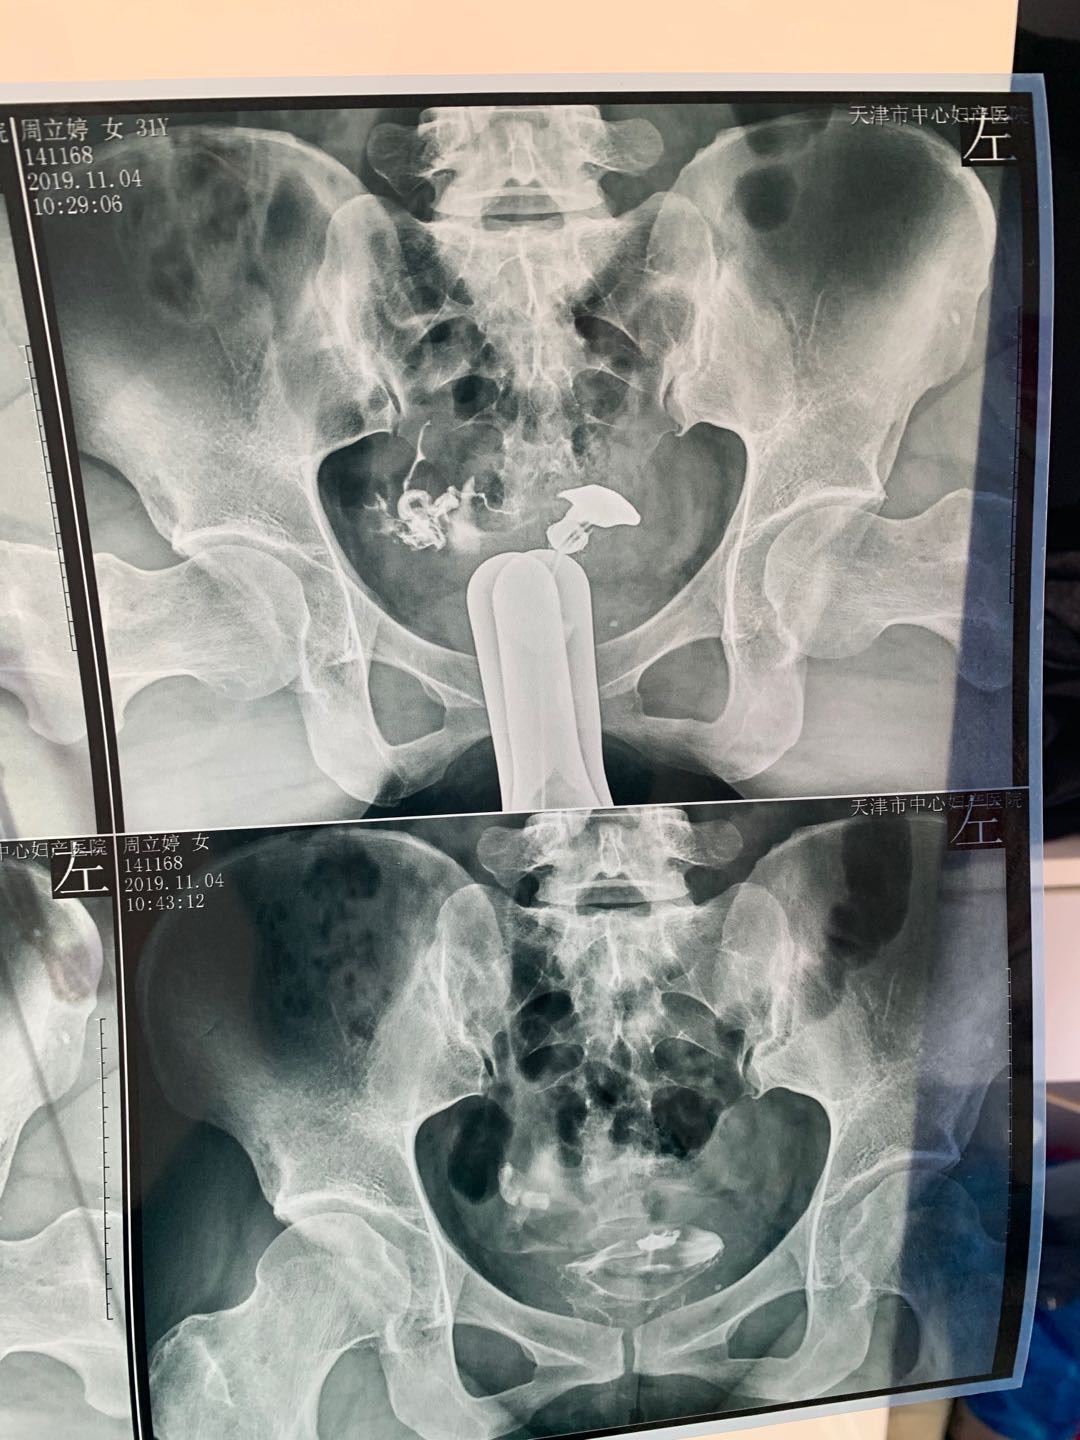

我今年34岁,右侧输卵管粘连,左侧宫外孕输卵

做完输卵管造影第六天了小腹还是感觉沉甸甸的如